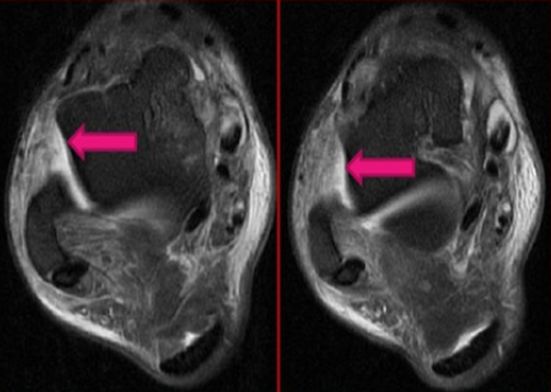

距腓前韧带撕裂

距腓后韧带撕裂

跟腓韧带撕裂